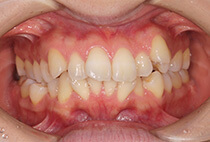

治療後

かみ合わせが整い咬筋の過緊張も改善しました。咬筋の肥大も治ってフェイスラインがすっきりしました。

最終的には美しい歯並びと、安定した痛みのないかみ合わせが実現しました。